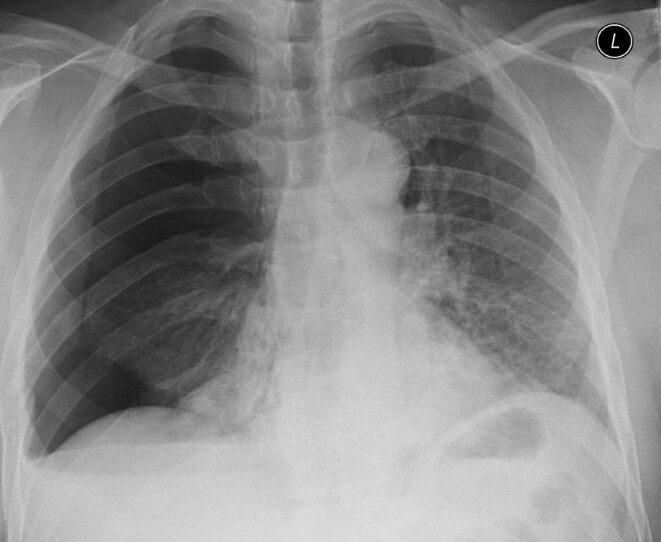

What is the diagnosis?

rib fracture